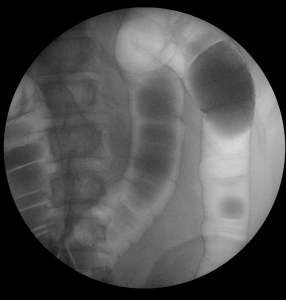

Vyšetření polykacího aktu, jícnu, žaludku, dvanácterníku a pasáž tenkým střevem

Jedná se o šetrnou metodu sloužící k diagnostice chorobných změn horní části trávicí trubice.

Kontrastní látka se pije ústy, vyšetření se provádí vestoje a vleže, průchod kontrastní látky lékař sleduje na monitoru a zachycuje na snímcích.

Jak je napsáno výše, nejčastější využití skiaskopie je při vyšetření trávicí trubice. Pro její zobrazení je nutné podání kontrastní látky. Nejčastější kontrastní látkou je baryová suspenze, která má různou hustotu, dle vyšetřované oblasti, má bílou barvu a chuť podobnou křídě, ve většině případů pro komfort pacienta doplněnou různými, převážně ovocnými příchutěmi. Při vyšetření se navíc používá plyn pro dosažení tzv. dvojího kontrastu – přímo aplikovaný při vyšetření tlustého střeva.